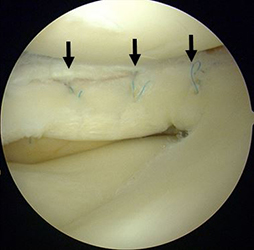

半月は、膝関節の大腿骨と脛骨の間にあるC型をした軟骨様の板で内側・外側にそれぞれがあり、クッションとスタビライザーの役割をはたしています。半月板損傷は、スポーツ外傷や加齢性の変化などにより、幅広い年齢層に生じます。症状は、引っかかり感や関節が曲がらない・伸びないなどの関節可動域制限、しゃがんだ際などの痛みであり、痛みがひどい場合には、夜間寝返りで目が覚めることもあります。半月板は損傷すると治りにくい組織です。保存的治療で症状改善が得られない場合、関節鏡視下の半月板部分切除術や縫合術をお勧めします。

関節鏡視下半月板部分切除術・縫合術

本手術は内視鏡を用いて行うため、少数の小さい傷で低侵襲に行う事ができます。可及的に縫合し半月板の温存を試みますが、損傷形態によっては部分切除を選択します。リハビリは、術翌日より積極的に行い、スポーツ復帰や社会復帰に向け準備致します。

前方に逸脱した外側半月板を整復し縫合した。